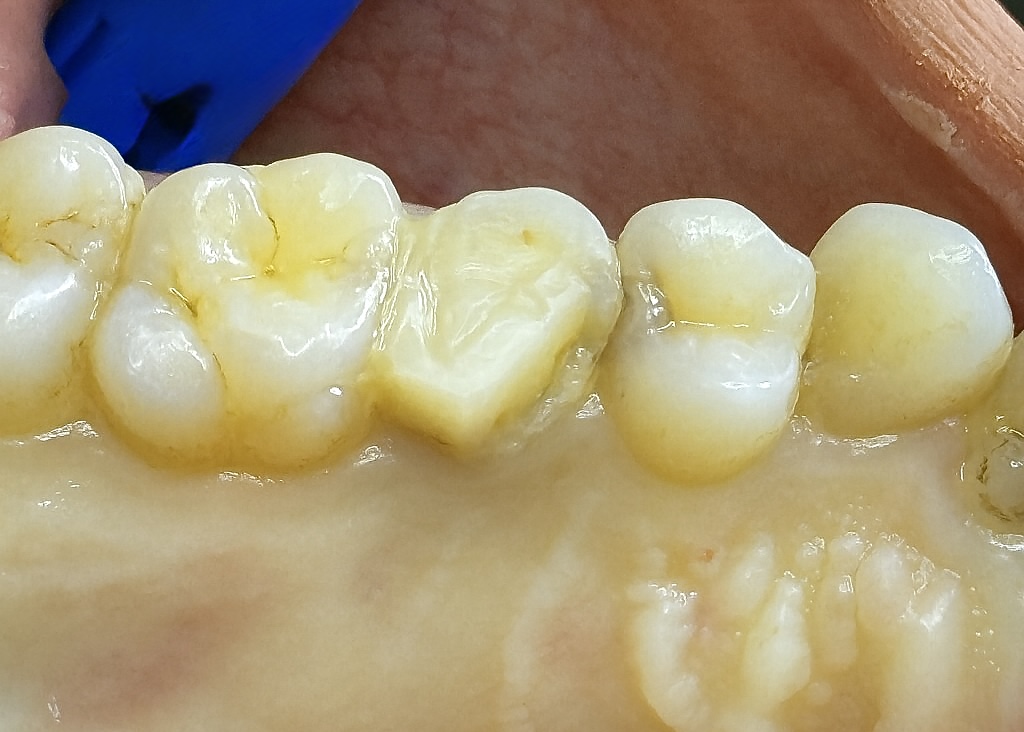

The patient presented with localized food impaction, deep caries in the lower right molar, and an endodontically treated premolar showing structural loss (Fig 1). A quadrant plan was developed to restore both teeth functionally and esthetically in a single session.

- Fig 1: Pre-operative quadrant showing caries and structural loss.